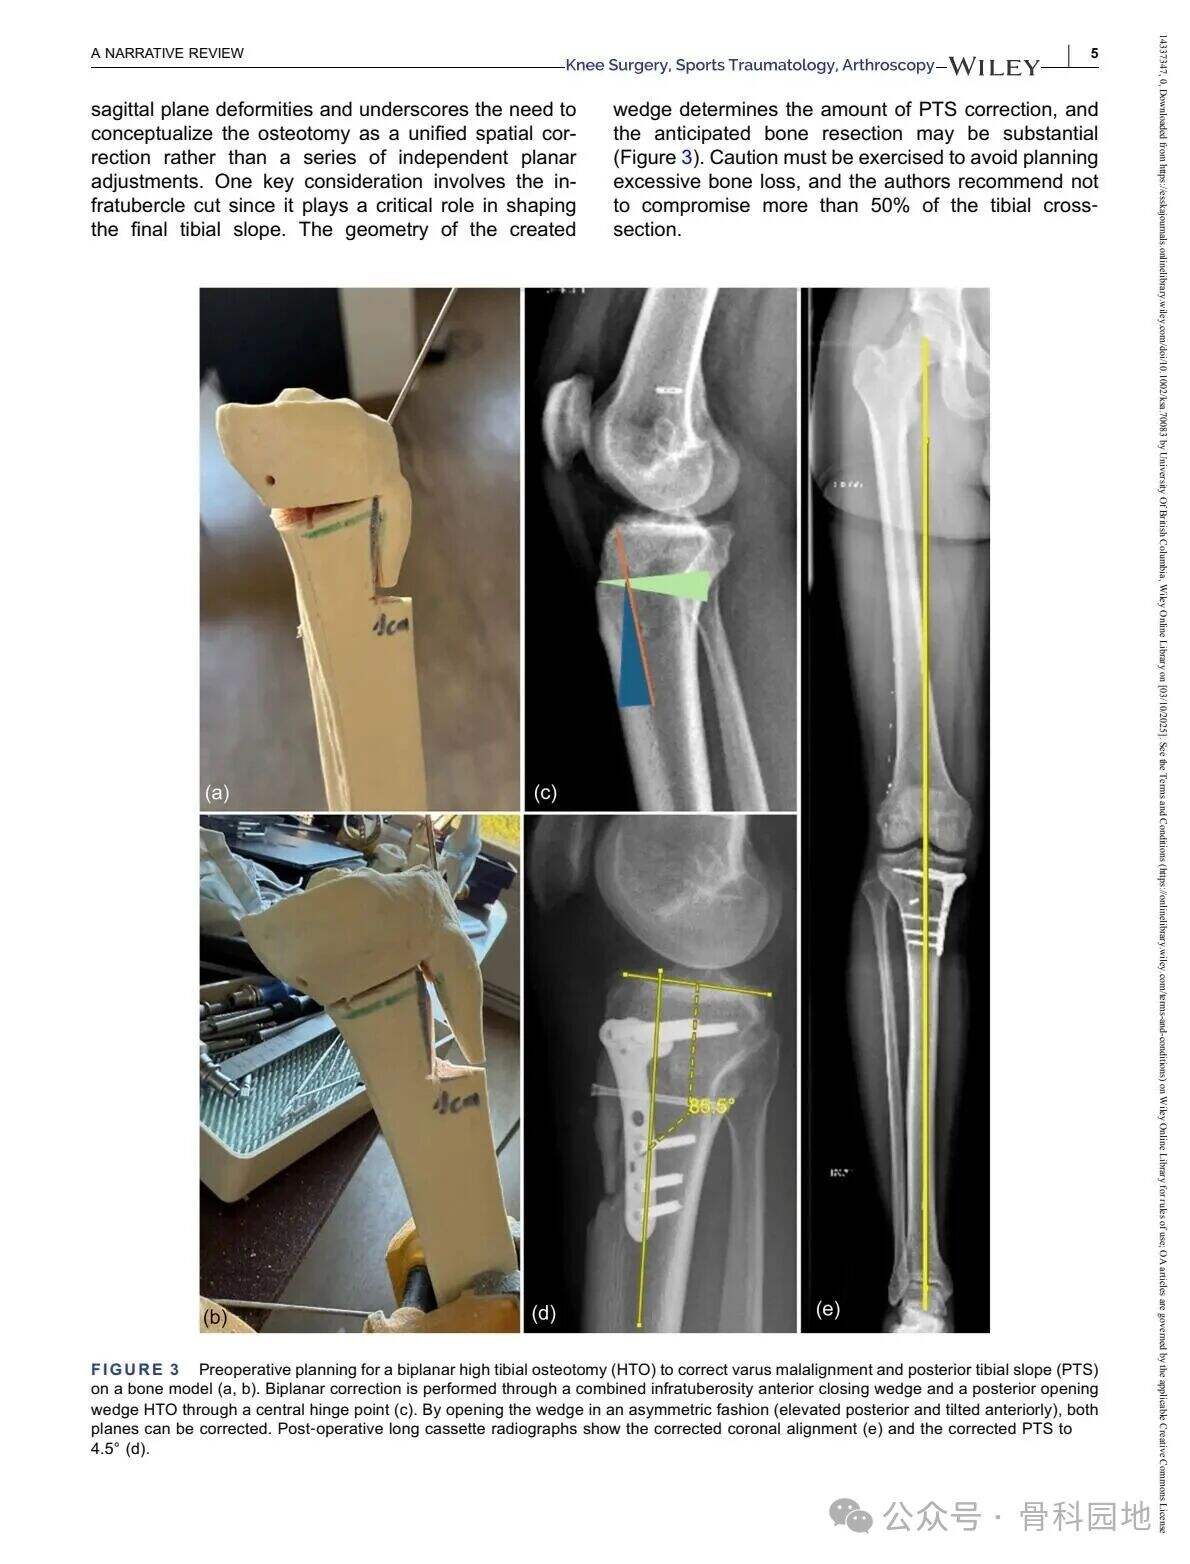

Čeprav konvencionalna visoka tibialna osteotomija (HTO) predvsem obravnava nepravilno poravnavo v koronalni ravnini, pomembnost poravnave v sagitalni ravnini – zlasti posteriornega tibialnega naklona (PTS) – ni mogoče prezreti v primeru nesposobnosti križnih vezi. Kombinirane nepravilnosti v koronalni in sagitalni ravnini so razmeroma redke in predstavljajo posebne kirurške izzive. Ta narrativni pregled povzema ustrezno literaturo ter predstavlja tehnične strategije za obravnavo zapletenih dvoravninskih nepravilnosti s pomočjo primerov iz prakse in razprav o različnih tehnikah.